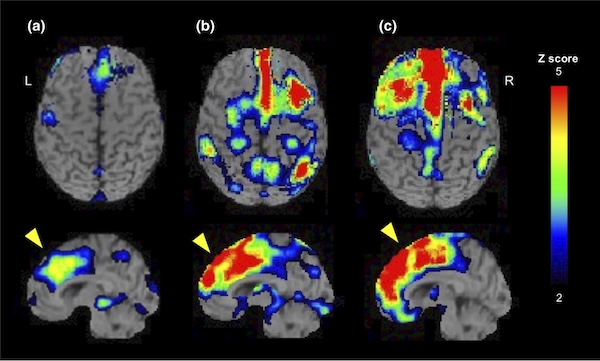

経軸索スフェロイド形成を伴う遺伝性びまん性白質脳症(hereditary diffuse leukoencephalopathy with spheroid:HDLS)の原因遺伝子であるcolony stimulating factor-1 receptor (CSF1R)遺伝子変異を有する症例、CSF1R関連白質脳症の脳血流についてSPECTを用いて解析しました。病期の進行とともに脳血流低下が,内側前頭皮質から外側前頭皮質,頭頂葉にかけて広がっていくことを示しました(NCN 2021)。

図. CSF1R関連白質脳症3名の脳血流の変化(eZIS解析)

(a)発症後 12ヶ月 (b)発症後 15ヶ月 (c)発症後 96ヶ月

発症とともに脳血流低下の領域が拡大していきます(NCN 2021)。